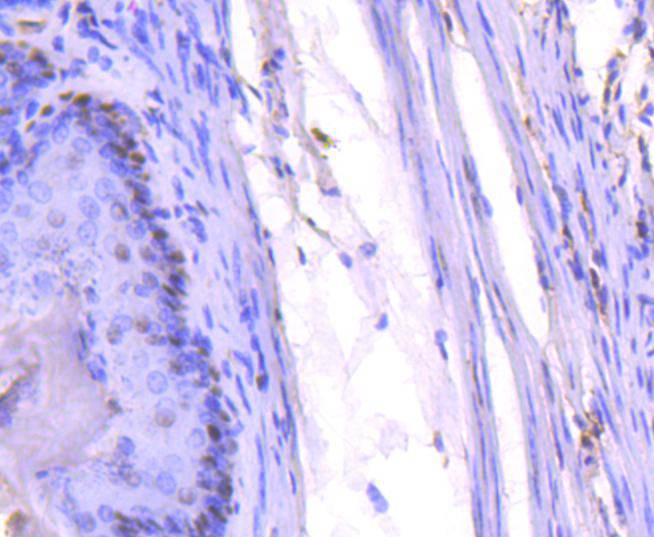

Immunohistochemical analysis of paraffin-embedded mouse colon tissue using anti-PCNA antibody. Counter stained with hematoxylin.

Immunohistochemical analysis of paraffin-embedded mouse stomach tissue using anti-PCNA antibody. Counter stained with hematoxylin.